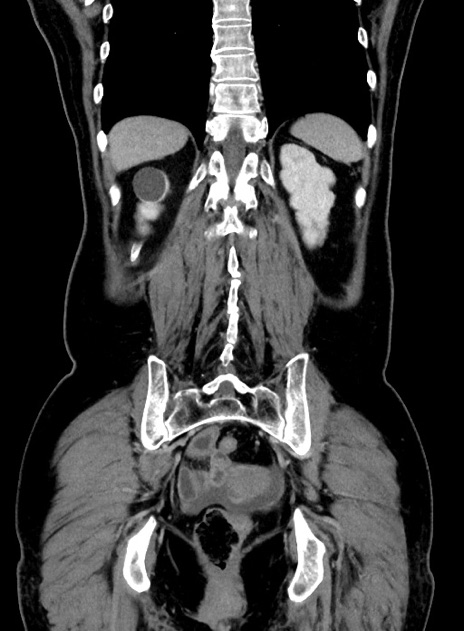

症例9(冠状断像)

【症例】 60歳代女性

【主訴】むかつき、みぞおちの痛み

【現病歴】3日前よりむかつきがあり、食事がとれない。

【既往歴】糖尿病

【身体所見】発熱なし、心窩部圧痛軽度あるも、腹膜刺激症状なし。

【データ】WBC 7400、CRP 1.92